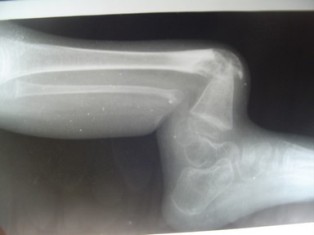

Fibrous Dysplasia is a rare skeletal disorder that affects bone development and growth. It occurs when normal bone tissue is replaced with fibrous tissue, resulting in weakened and irregularly shaped bones. This condition can affect one bone (monostotic) or multiple bones (polyostotic), and it may manifest in childhood or adulthood. While theexact cause of Fibrous Dysplasia is not fully understood, it is often attributed to genetic

mutations.

Bone Deformities: The affected bones may become deformed, leading to an uneven appearance, unequal limb lengths, and a higher susceptibility to fractures.